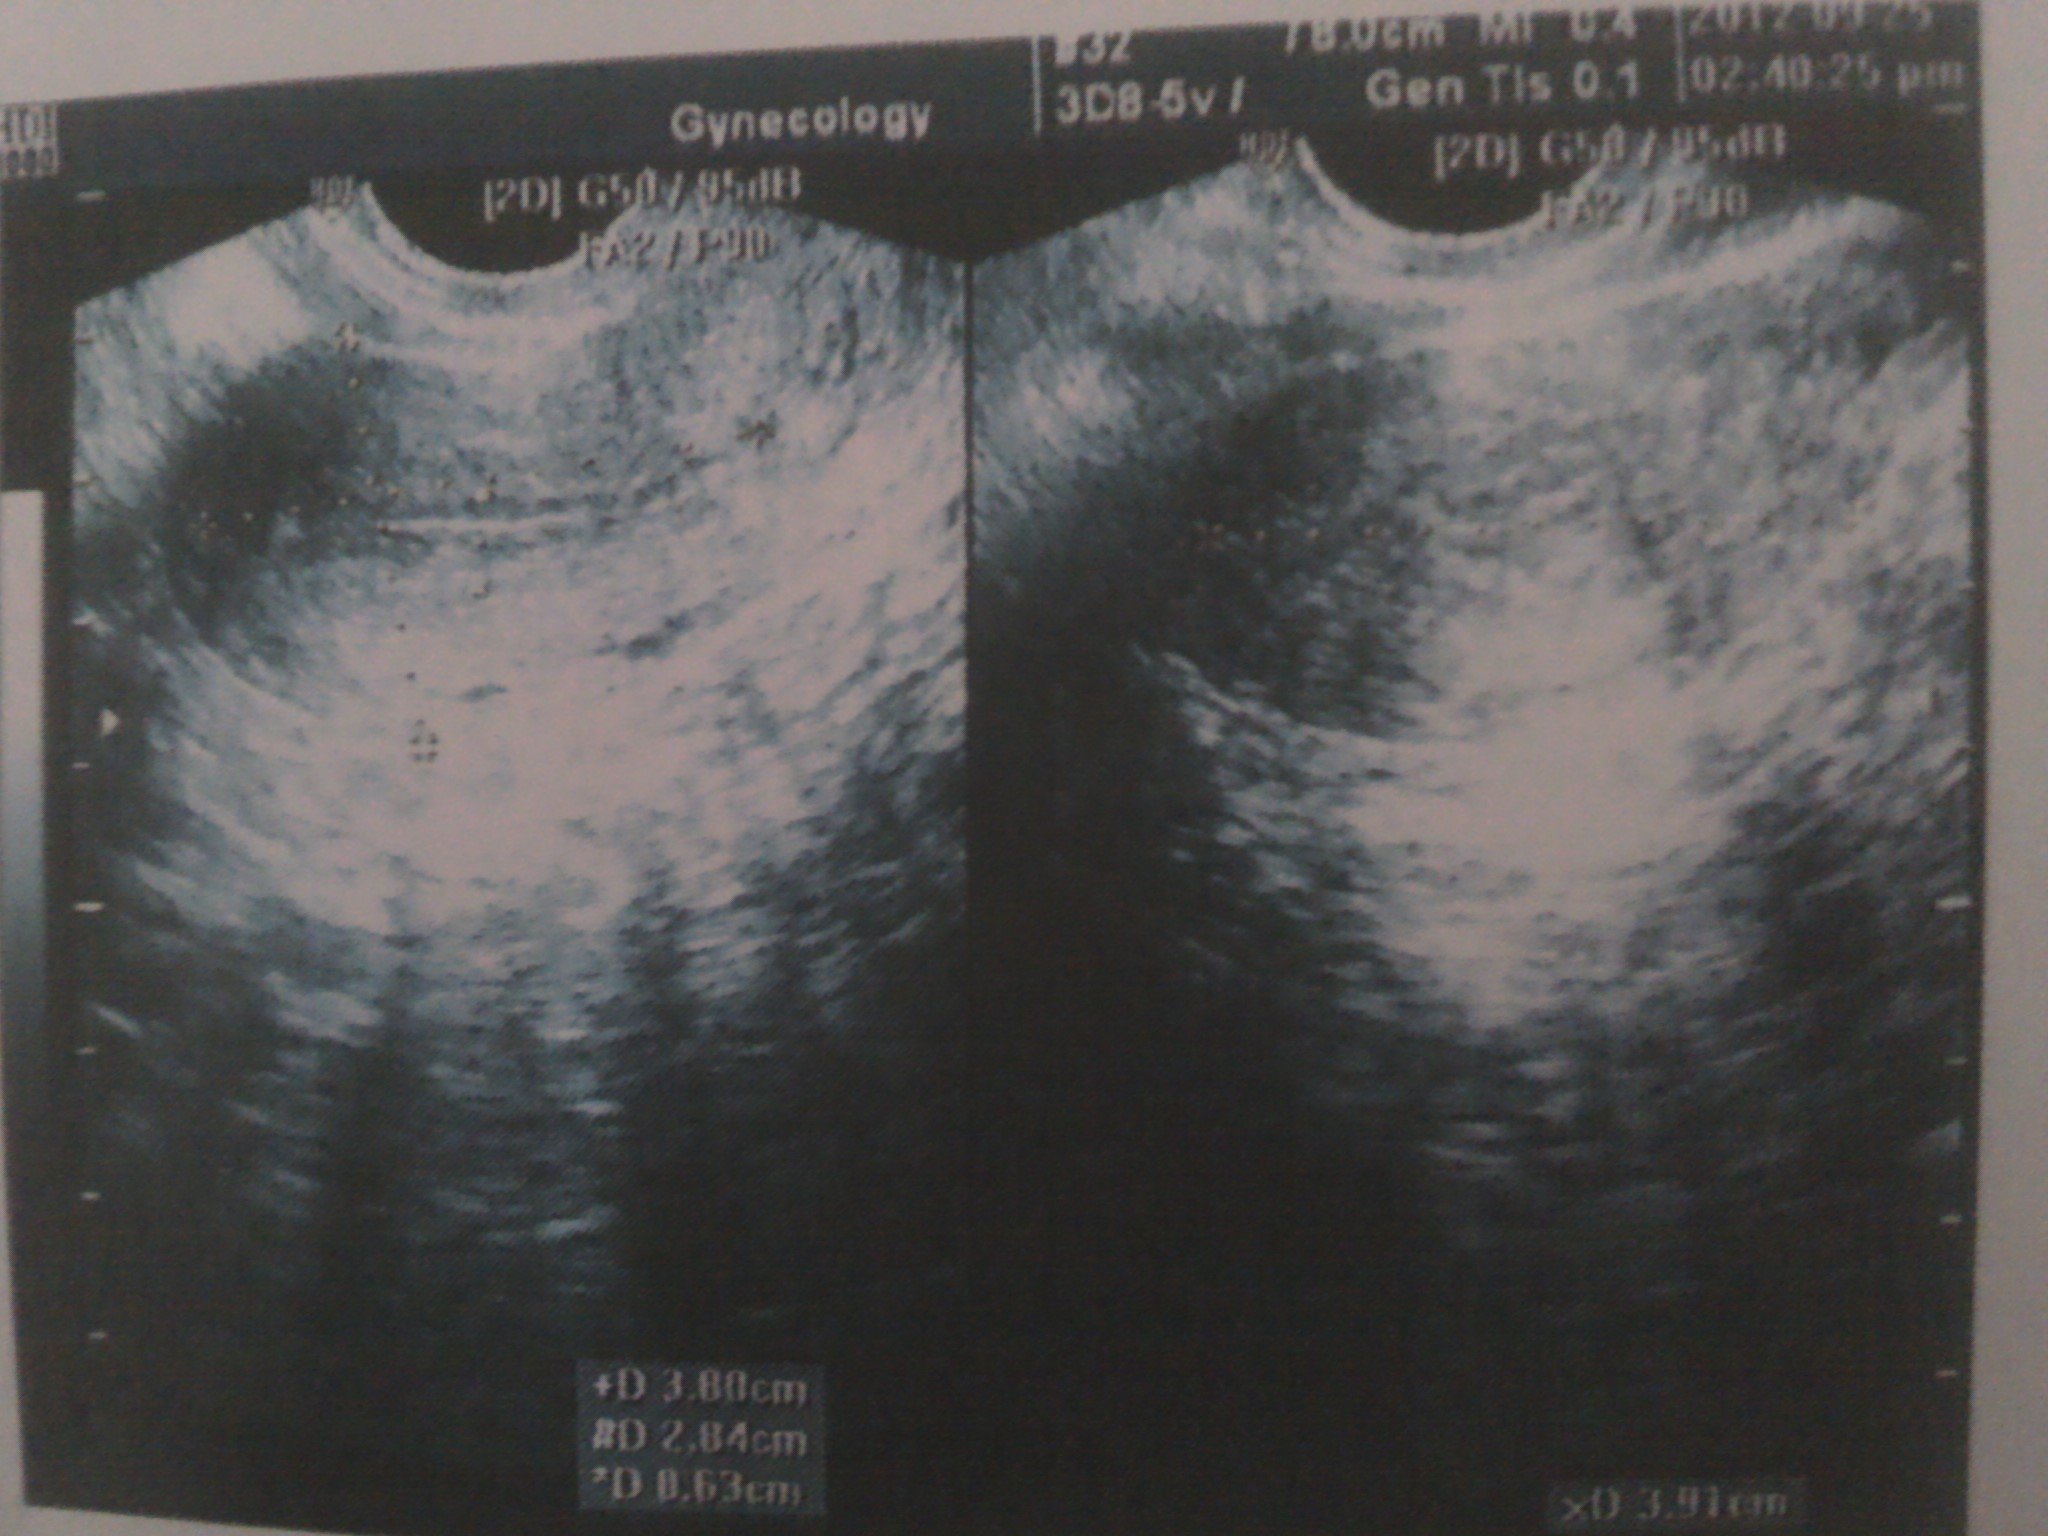

患者信息:女 31岁 辽宁 本溪 病情描述(发病时间、主要症状等):图1,图2,图3,是2012年6月30日拍的。超声所见:子宫前位,大小约4.6*3.6*3.6cm,肌层回声均匀。内膜厚约0.6cm。 左侧卵巢大小约2.5*2.1cm,内见2.4*2.0囊性暗区。 右侧卵巢大小约3.8*3.7cm囊性暗区,囊壁光滑,囊液透气好。诊断意见:左卵巢囊性结构,右卵巢囊肿—————————————————————————————————图4,图5,图6 是2012年9月25日拍的超声描述:子宫体大小约:3.8*3.9*2.8cm 子宫前位,轮廓清晰,光滑,肌层回声均匀,内膜厚约0.6cm 左卵巢大小约:3.2*1.6cm,右卵巢大小约:2.6*1.8cm,双附件区均可见无回声团,形态不规则,大小分别约5.8*2.9*3.5cm(左侧),6.2*3.2*3.4cm(右侧) 宫颈厚约2.2cm,回声较均匀。超声提示:双侧附件区囊性包快(考虑输卵管积液)想得到怎样的帮助:未婚,打算要孩子。这两次检查相差三个月,之前检查,都没说有输卵管积液。这次医生态度很严肃,说输卵管造影和通水现在都没用了。让我做腹腔镜,考虑试管婴儿。我的情况非常严重吗?怎么治疗?能看出我是哪种囊肿吗曾经治疗情况及是否有过敏、遗传病史:没治疗过。